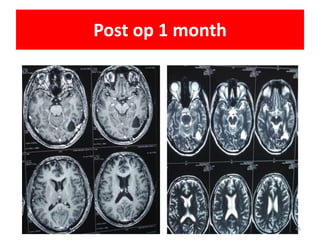

Post op 1 month

45

• NAME • UMR •PRESENTATION • SEIZURES, UNCONSCIOUS • MRI • 3.2X3.2CM, LEFT OCCIPITAL LOBE,EDEMA,CONTRAST ENHANCEMNET • SURGERY • TOTAL EXCISON • BIOPSY • METASTATIC PAPILLARY ADENOCARCINOMA • PET CT • RT LUNG LESION • MULTIPLE NODULE BOTH LUNG • LESION IN BRAIN • MEDIASTINAL NODE • SRS • CAVITY SRS 30Gy/5# • IHC • EGFR+VE • EXON21 MUTATION • ALK NEG • TTF1 +VE • CHEMO • PEMETRXED AND CARBOPLATIN • OMERTINIB 80MG Case details 43

Post op 1month 45